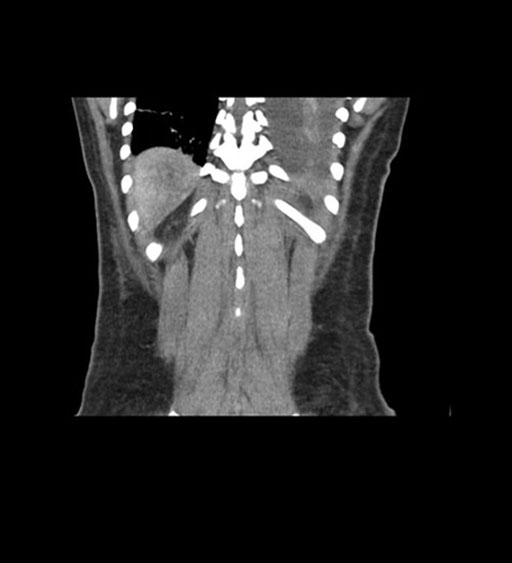

Coronal Venous